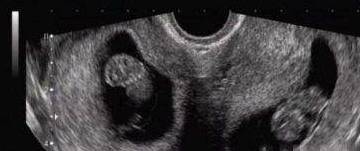

肚子里怀上了两个孩子,B超也看到了孩子的身影,到生产的时候孩子却没有了,子宫变成了空的,这是怎么回事呢?

在场的医生立马为他做了一次全面的检查,检查的结果让在场的人惊出了一身冷汗。小赵的子宫是空的,没有胎儿,但是B超里确实看到还有一个孩子,而且这个孩子已经有10个月大了。这个孩子到底在哪里呢?

又经过仔细的检查,原来小赵竟然是双子宫,另一个孩子在另一个子宫里呢,现场的人终于松了一口气!